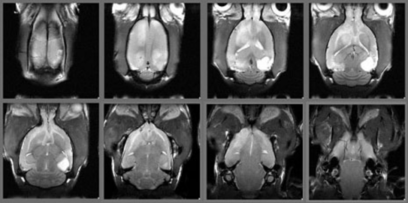

コモンマーモセットの脳の画像

コモンマーモセットの前額断T2強調画像